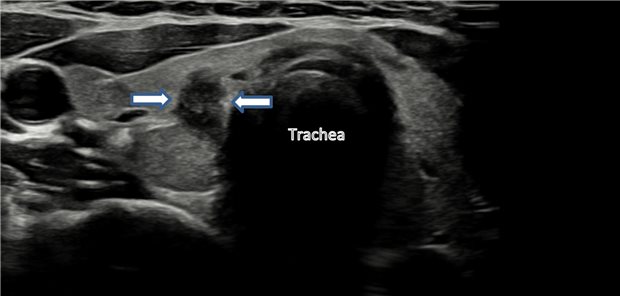

Ist der Knoten ein Schilddrüsenkarzinom? Das sind die ersten Schritte zur Abklärung